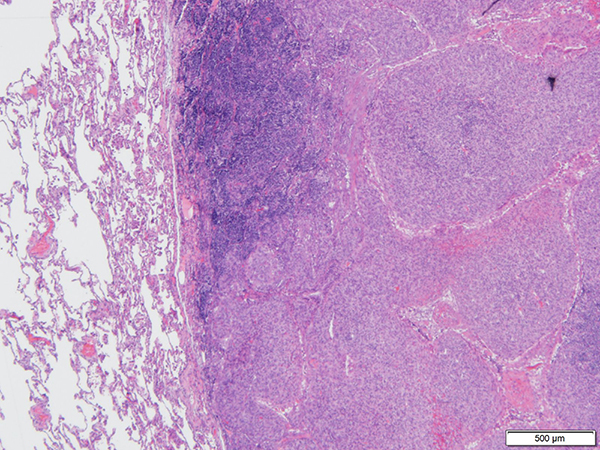

Clinical History: A 59-year-old man was found to have 1.5-cm heterogeneous, non-calcified lung nodule in the left lower lobe on a surveillance CT scan, a year after a right hemicolectomy for a malignant mesothelioma. The nodule was sampled by a transthoracic core needle biopsy and fine-needle aspiration. The biopsy and FNA showed a dense fibrous pseudocapsule surrounding nodules of histiocytoid cells arranged in sheets, whorls, and short fascicles with round normochromatic nuclei, inconspicuous nucleoli, and vacuolated cytoplasm with associated lymphoid aggregates around the nodules (Figures 1 to 6). The neoplastic cells were positive for CD68, focally positive for desmin, and negative for EMA, pancytokeratin, CD21 and calretinin. A diagnostic molecular test was performed.

Grossly, pulmonary AFH is similar to those arising in the soft tissue and demonstrates a nodular, well-circumscribed, and hemorrhagic cut surface. These tumors can also be multi-cystic. The median size is around 2 cm. Microscopically, AFH is encapsulated, with a dense fibrous pseudocapsule and associated lymphoid aggregates (mixture of B- and T-lymphocytes) around nodules, and often hypercellular with bland histiocytoid cells. Most cases have large, round, blood-filled spaces associated with surrounding hemosiderin deposition in the center of the lesion; although approximately one-third of cases show completely solid histology without these above-mentioned cavities. The cells surrounding the cystic spaces are uniform with monomorphic spindle to ovoid cells and eosinophilic cytoplasm. Occasionally, mitotic activity and pleomorphism can be seen; however these features are not associated with a worse outcome. The stroma can be myxoid or sclerotic, mimicking the desmoplastic stroma of a carcinoma. The cytopathologic features of AFH include histiocytoid cells in sheet, clusters or individual cells admixed with eosinophilic mesenchymal fragments and lymphocytes in the background of blood. Lesional cells may have pleomorphism with abundant cytoplasm and prominent nucleoli.